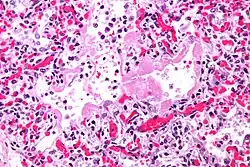

Micrograph showing hyaline membranes, the key histologic feature of diffuse alveolar damage. H&E stain.

• Diffuse alveolar damage (DAD): an acute lung condition with the presence of hyaline membranes.[2] These hyaline membranes are made up of dead cells, surfactant, and proteins.[1] The hyaline membranes deposit along the walls of the alveoli, where gas exchange typically occurs, thereby making gas exchange difficult.

• The edema contributes to the deposition of a hyaline membrane (composed of dead cells, surfactant, and proteins) along the alveolar walls. Hyaline membranes are characteristic of DAD.

In order to make a diagnosis of DAD a biopsy of the lung must be obtained, processed, and examined microscopically. As described above, the hallmark of diagnosing DAD is the presence of hyaline membranes.[1] Most frequently DAD is associated with ARDS, but since there are clinical criteria (see Berlin criteria above) upon which we can diagnose ARDS, it is often unnecessary in all cases to obtain invasive biopsies of the lung. Additionally, there are limitations of the biopsy test since it is possible to sample a potentially normal area of lung even though there is DAD in the rest of the lung, resulting in a false negative.[1]